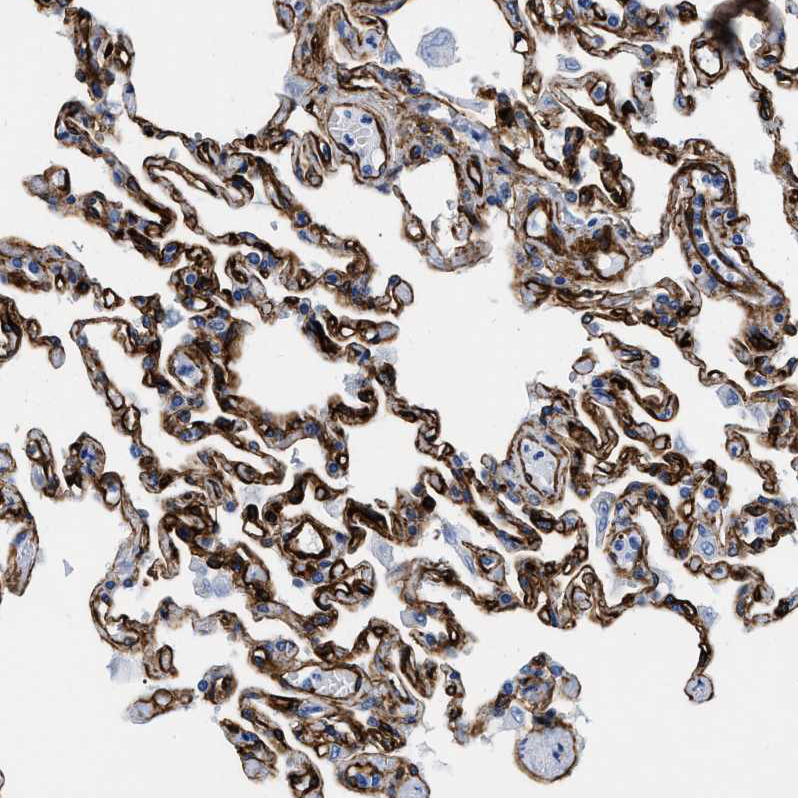

Immunohistochemical staining of human lung shows strong membranous positivity in pneumocytes.